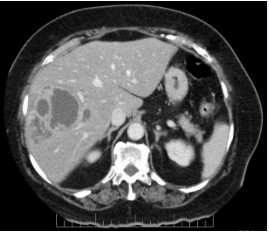

USG W/A and HRUSG of the swelling and USG W/A showed multiple splenic abscess with largest measuring 14*16 mm and HRUSG revealed 12*15 cm abscess with multiple internal septations.

FIG 3:RADIOLOGY OF LIVER ABSCESS